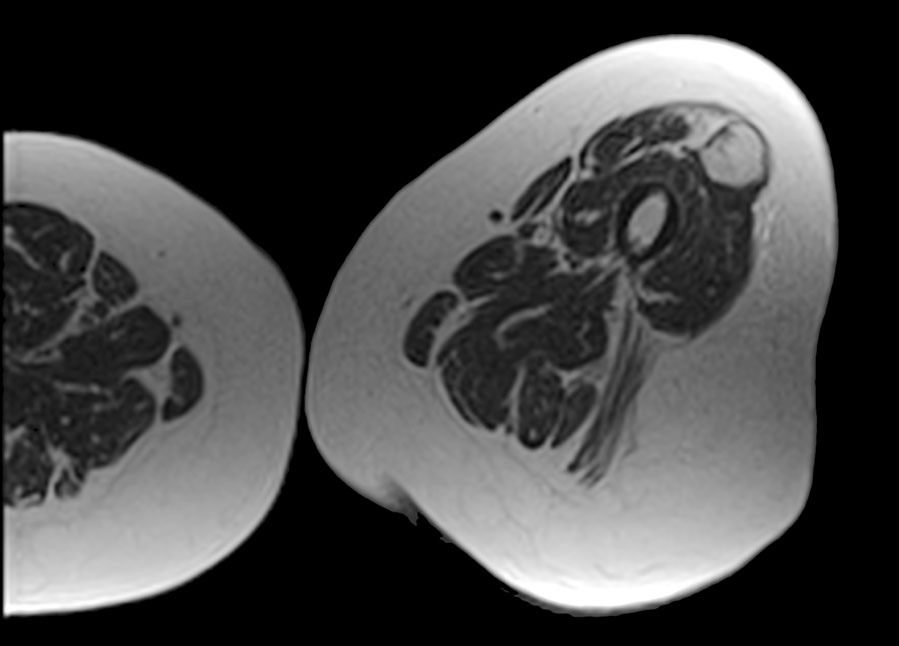

SmartTARGET TM

MRI İLE IŞIN KONTROLÜ

Tümörler veya yakındaki kritik yapılar aniden pozisyon değiştirdiğinde, MRIdian’ın gerçek zamanlı 3D doku takibi ve otomatik radyasyon ışını kontrolü sayesinde anında tepki vererek radyasyonu otomatik olarak kapatarak kritik yapılardan kaçınırken öngörülen dozların hedefe ulaşmasını sağlar. Aynı şekilde, tümör konumuna döndüğünde, ışını otomatik olarak tekrar açılır.

SmartTARGET TM

MRI İLE IŞIN KONTROLÜ

Tümörler veya yakındaki kritik yapılar aniden pozisyon değiştirdiğinde, MRIdian’ın gerçek zamanlı 3D doku takibi ve otomatik radyasyon ışını kontrolü sayesinde anında tepki vererek radyasyonu otomatik olarak kapatarak kritik yapılardan kaçınırken öngörülen dozların hedefe ulaşmasını sağlar. Aynı şekilde, tümör konumuna döndüğünde, ışını otomatik olarak tekrar açılır.